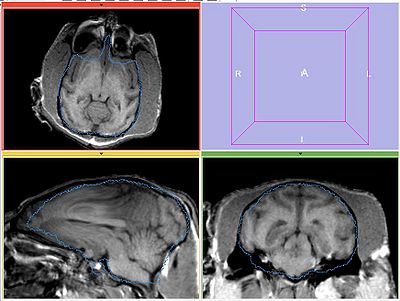

The following screeshots demonstrate good initial alignment of the images with the initial affine transformation, and the outline of ROIs. Also note that FIXED1 and FIXED2 are very similar within ROI.

MOVING (under INITIAL_TFM)